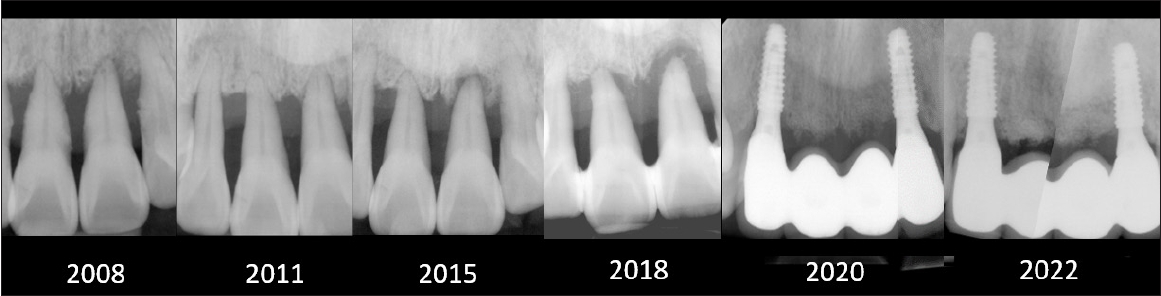

The proportion of sites with PD ≥4 mm decreased progressively over the years: 33% at baseline, 14% in 2004, 12% in 2018, and 9% in 2022 (Fig. 1). All natural teeth were preserved except for the maxillary right second molar. Serial radiographs demonstrated stable periodontal support and function throughout the 35-year follow-up period (Fig. 2).

Serial periapical radiographs of the maxillary anterior region from 2008 to 2022 (year 14). Repeated non-surgical periodontal therapy contributed to relatively stable bone levels around the central incisors. Following a trauma in 2015, apex-involved bone resorption developed in the left central incisor, ultimately leading to extraction and subsequent implant placement.